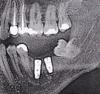

VEB Опубликовано 14 мая, 2012 Поделиться Опубликовано 14 мая, 2012 Здравствуйте. 3 месяца назад установили 2 импланта. Импланты не беспокоят и не беспокоили, после операции был не большой отек, через 3 -4 дня спал полностью.Сейчас сделал понорамный снимок, с доктором еще не общался, но по снимку мнекажется, что импланты не прижились? Снимок отпечатан на бумаге был, поэтому качество не очень, наверное.Если не прижились, из за чего могло такое случится?Подскажите, пожалуйста. Ссылка на комментарий

kriokov Опубликовано 14 мая, 2012 Поделиться Опубликовано 14 мая, 2012 Щель между имплантатами и костью на снимке может быть так называемым фоном от имплантатов (особенностью снимка и его отпечатка на бумаге) . Не паникуйте, лучше с доктором пообщяйтесь 1 Ссылка на комментарий

VEB Опубликовано 14 мая, 2012 Автор Поделиться Опубликовано 14 мая, 2012 Щель между имплантатами и костью на снимке может быть так называемым фоном от имплантатов (особенностью снимка и его отпечатка на бумаге) . Не паникуйте, лучше с доктором пообщяйтесь Надеюсь. Такой же фон заметен около пломбы зуба, и в других местах снимка. Ссылка на комментарий

Bier Опубликовано 15 мая, 2012 Поделиться Опубликовано 15 мая, 2012 радиолюценция, имплантаты на цифровом орто всегда так выглядят. 1 Ссылка на комментарий